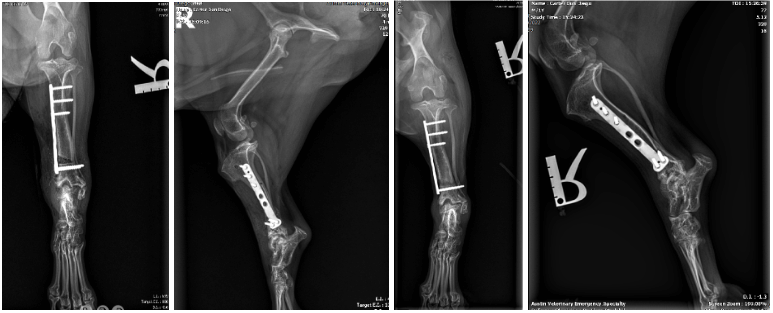

Distal Tibial Opening Wedge Corrective Osteotomy

Ambulatory, with no apparent lameness at a walk or trot. Nonpainful range of motion of the tarsus and stifle. Healing osteotomy with no radiographic evidence of complications.